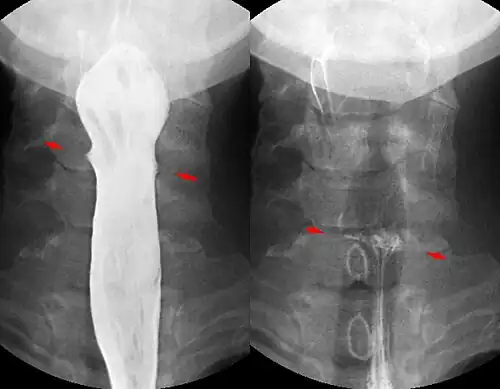

Fishbone pierced in the upper esophagus.Left image during swallowing contrast medium, right image after swallow only dimly visible.